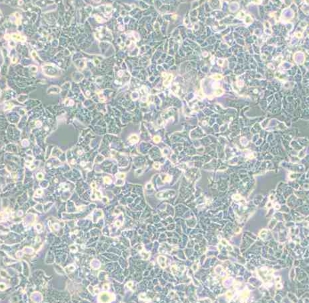

1. 形态特征:上皮细胞样,贴壁生长;细胞形态均一,呈多边形。